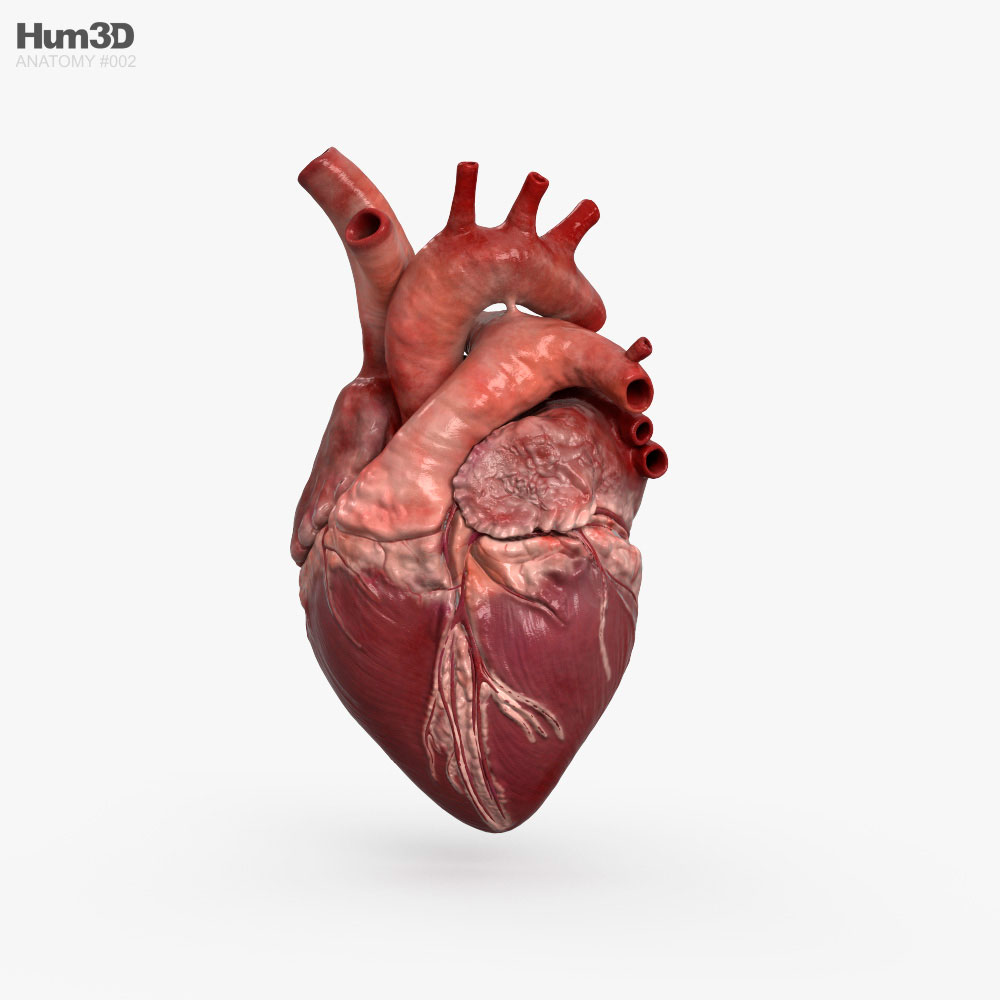

Heart Anatomy Human Heart Images Hd 3D - Dreaming Arcadia  Anatomical Heart Drawing at GetDrawings | Free download

Detailed 3D Human Heart | CGTrader  3d human heart

3D human heart model - TurboSquid 1149348  Get Easy Pencil Heart Art Easy Pencil Heart 3D Drawing Gif â Drawing 3D Easy

Human Heart Anatomy 1 3D model | CGTrader  How to draw realistic human heart||3d human heart sketch

3D Human Heart animated | CGTrader  How the Human Heart Works | Safety and Health Solutions

Heart Anatomy Human Heart Images Hd 3D - Dreaming Arcadia  Realistic Human Heart 3D model | CGTrader

Realistic Human Heart 3D model | CGTrader  anatomy human heart 3d c4d

anatomy human heart 3d c4d  Human Heart Section 3D model | CGTrader

3D human heart - TurboSquid 1737445  How to Draw a Human Heart - Really Easy Drawing Tutorial

Image of Human Heart 3D Illustration | Stock Image MXI28575  The human heart by SkarlettFury on DeviantArt | Human heart drawing, Heart drawing, Heart art

Human Heart Anatomy 1 3D model | CGTrader  human heart anatomy 3d max

human heart anatomy 3d max  Heart Anatomy Human Heart Images Hd 3D - Dreaming Arcadia

Heart Anatomy Human Heart Images Hd 3D - Dreaming Arcadia  Pin on Body Parts Drawings